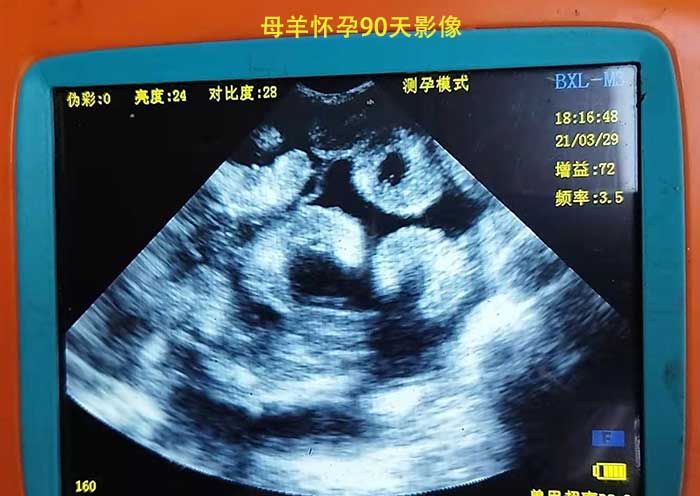

四川内江羊用B超价格多少?给母羊测孕用的B超机有四五千的,七八千的,还有上万的,多少钱的都有?它们z明显的区别就在于功能,还有图像清晰度上面,例如BXL-M3和BXL-V10这两款都是体外给母羊测孕的,BXL-V50和BXL-V60这两款配有羊直肠专用探头可以体内测孕,且有上门培训,主机配置更高,显示屏是8寸的高清液晶大屏,之前的B超机只是探头防水,这两款是整机防水的,且一次充电可以用6-7小时左右。15515670076

母羊怀孕影像特征

母羊怀孕44天主要特征:在超声图像上可以看到子宫区域内有一个胎囊,胎囊内有无回声暗区的胎水,胎水内可以看到回声较强的胎体结构。

母羊怀孕56天主要特征:此阶段可以看到有很多子叶的出现,胎囊很明显,胎儿的骨骼开始呈现出较强的回声现象,胎儿的心跳可以很容易的辨别出来。

母羊怀孕63天主要特征:子叶抓紧变大,胎囊也逐渐的增大,子叶的大小是判断胎龄的重要要素,胎儿的脊椎骨在此时可以清楚的看到。